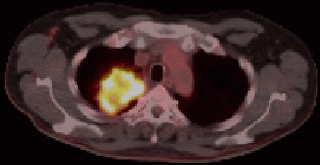

blauer Punkt 72-jähriger Mann, bei dem vor 2 Jahren ein Plattenepithelkarzinom des rechten Mittellappens operiert wurde. Bei asymptomatischem Verlauf im PET-CT ein Rezidiv im oberen rechten Hilus. Bronchusabsetzungsstelle frei!